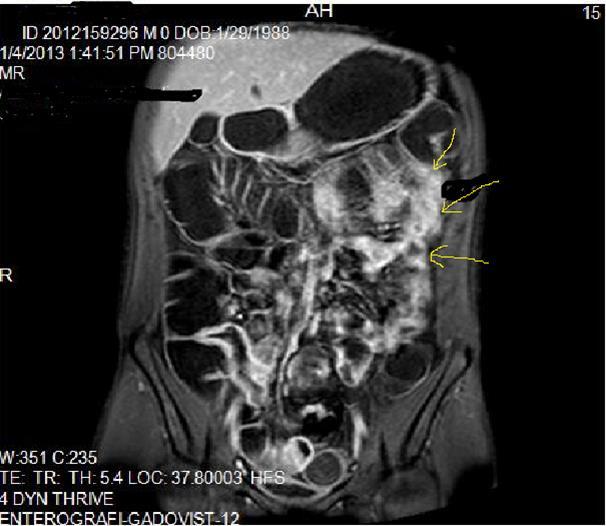

Pathognomonic signs of Crohn’s disease are; Bowel wall thickness must be higher than 2 mm in small intestine, 3 mm in colon, valvula conniventes has to be less than 3 mm, and small intestine diameter will be less than 3 cm, long segment intestinal infiltration, creeping fat sign, loss of haustration in colonic segments, skip lesions between normal and diseased segments and transmural invasion of bowel wall2, 5, 12, 14,18, 19, 20. In endoscopy; Aftos ulcerations and erosions are found out initially in the normal bowel mucosa than at later stages, mural stratification with longitudinal and transverse ulcerations are observed7, 14, 20, 21. On MRI; High bowel wall enhancement is particular at active inflammation, increased signal at bowel wall and adjacent mesentery on T2W images, strictures-fistulization and abcesses are the main complications and hyperintense on T2W images, asymmetrically thickened mucosal folds and lymphadenopathy, mesenteric stranding of the effected bowel wall and prominent draining vessels of the inflamed intestinal loops(comb sign), presence of intramural fat at chronic phase and target sign due to wall thickening at acute phase, surrounding peri-intestinal edema in acute phase are the main findings of Crohn’s disease7, 12, 14,18, 19, 20, 21 (Figure 2a-b)

Mucosal irregularities and ulcerations, strictures and fistulas at chronic stage can also be visualized by enteroclysis3, 4, 14, 15, 22 (Figure 3a-b-c).Clinical signs of Crohn’s disease are; Abdominal ache, diarrhea, fever, loss of weight, malnutrition, hemorrhage and fistulas, its extra-intestinal manifestations are: Arthritis, iridocyclitis, erthytema nodosum, aftoz stomatitis, cholelithiasis, primary sclerosing cholangitis and ankylosing spondylitis8, 9, 10, 11, 12, 13, 14, 15, 16,20, 21, 22.In the differential diagnosis; Ulcerative colitis(UC), ischemic colitis(IC), infectious-fungal and tuberculous(Tbc) enteritis, radiation enteritis, Lymphoma, Behcet’s disease have to be thought5, 6, 7,18, 19, 20, 21 . UC involves the entire colon, small intestine involvement is extremely rare, it tends to involve only the mucosal part of bowel with continuous pattern and skip lesions-transmural pattern of Crohn’s disease involvement can never be seen in UC, fistulization and abscess formations are not evident, terminal ileum involvement of UC is named as backwash ileitis, UC is a pre-malignant inflammatory disease which often causes rectal adenocarcinoma, Malignant transformation of Crohn’s disease is extremely rare 6, 8, 10, 14, 18, 19

Figure 2a.Concentric luminal narrowing, mural and transmural involvement of terminal ileum due to Crohn’s disease in T2W coronal sequence after OCA application.

Figure 2b.Curvi-lineer, diffuse peripheral enhancing bowel wall in the terminal ileum on axial T1W post-contrast image.

Figure 3a-3b-3c.Diffuse mucosal involvement and extreme luminal narrowing in the terminal ileum due to Crohn’s disease on T2W coronal sequence after OCA administration, stricture and string sign near ileo-ceccal valve in Figure 3b.